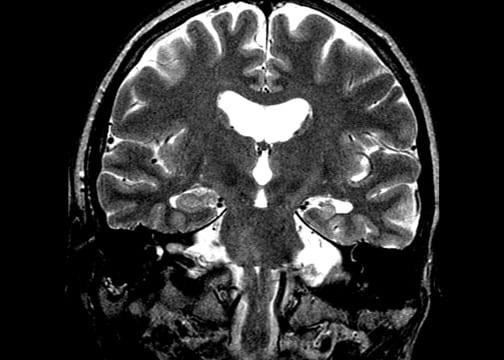

Check out some radiographic images of mesial temporal sclerosis from our image database: